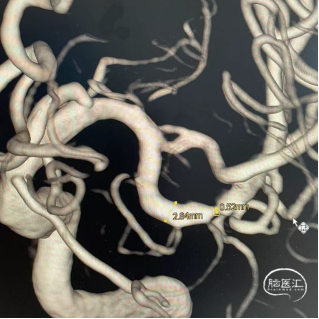

术前影像

头颅MRA示:左侧大脑中动脉M2段重度狭窄。

CTA进一步明确:左侧大脑中动脉M2重度狭窄。

头颅CTA:左侧大脑中动脉M1分叉后段局限性显影浅淡。双侧颈内动脉颅内段管壁稍毛糙,可见多发钙化斑块。左侧颈内动脉C6段轻度狭窄,右侧颈内动脉C6段轻-中度狭窄。双侧后交通动脉纤细。余头颈部血管未见明显异常改变。